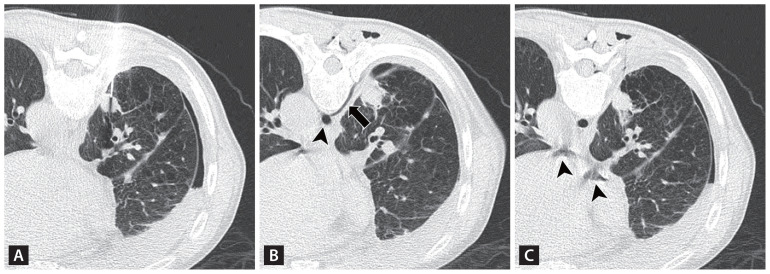

Systemic venous air embolism after percutaneous lung biopsy.

经皮肺活检后的全身静脉空气栓塞。